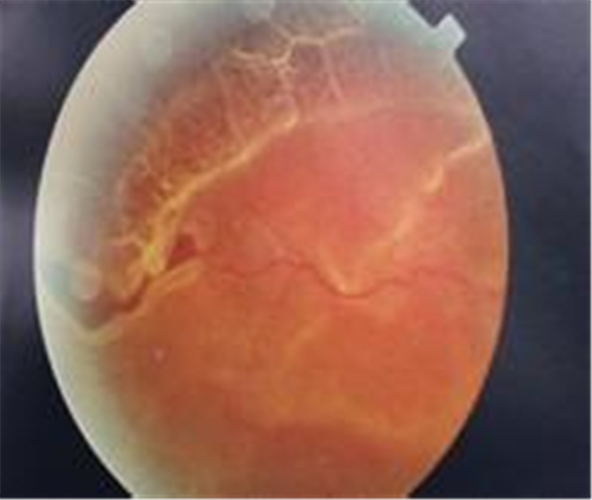

視網膜脫落圖片

視網膜脫落組圖